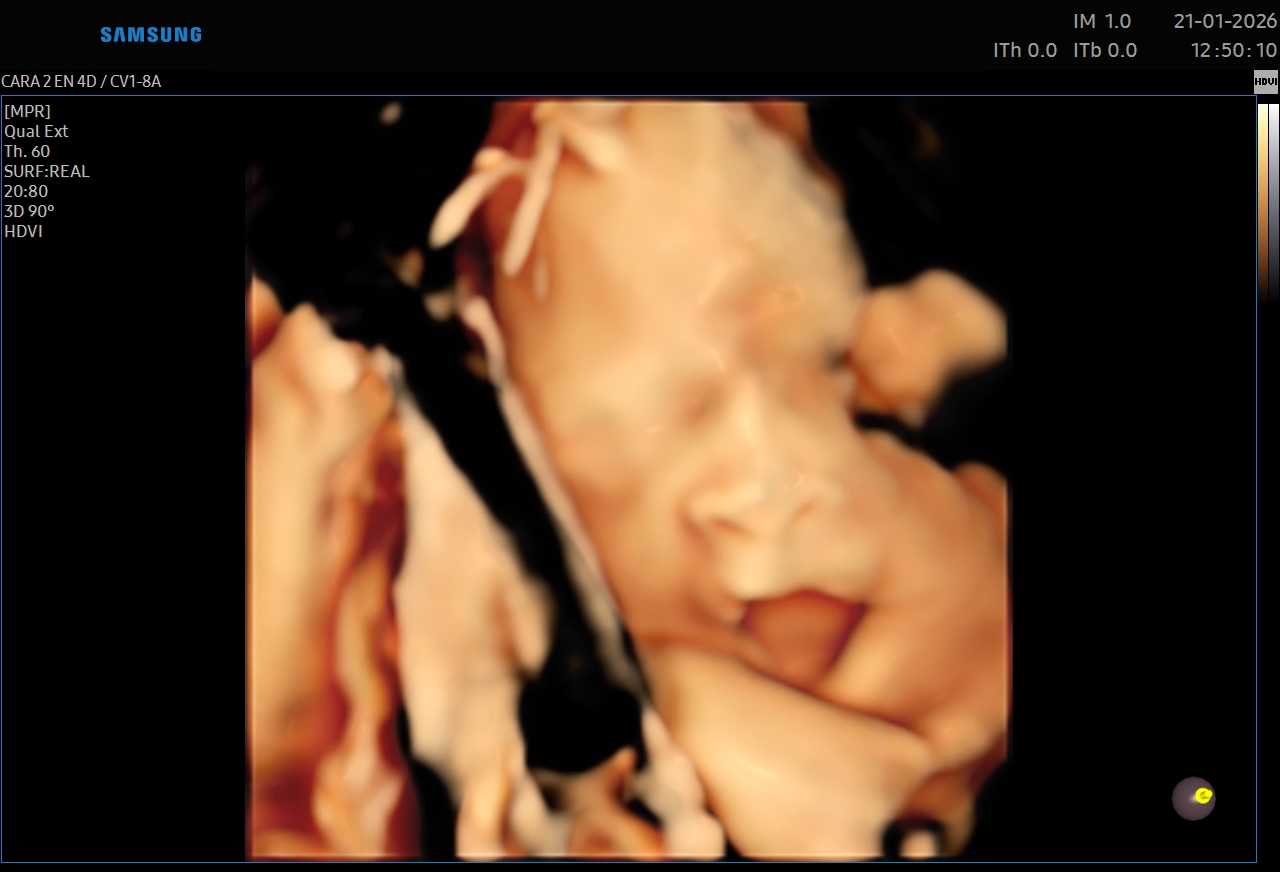

Ecografías 5D

Leer más